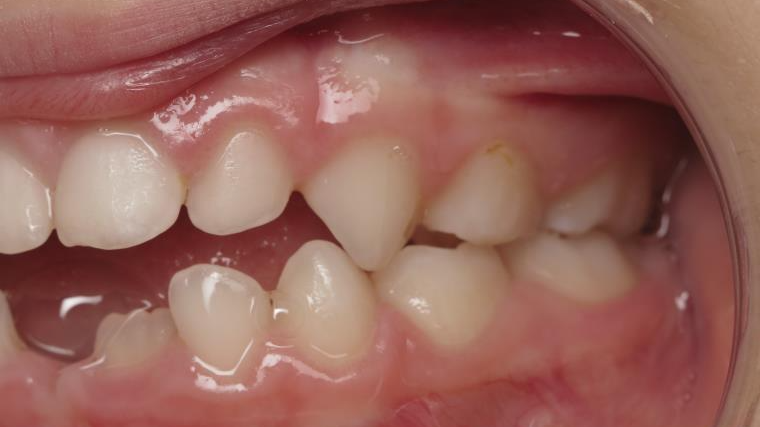

appareillage mobile pendant 14 mois

sectionnel multibagues pendant 8 mois